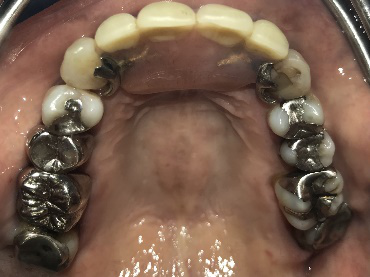

Before

インプラント埋入前

義歯を装着したところ

使用していた部分入れ歯

After

インプラント埋入後